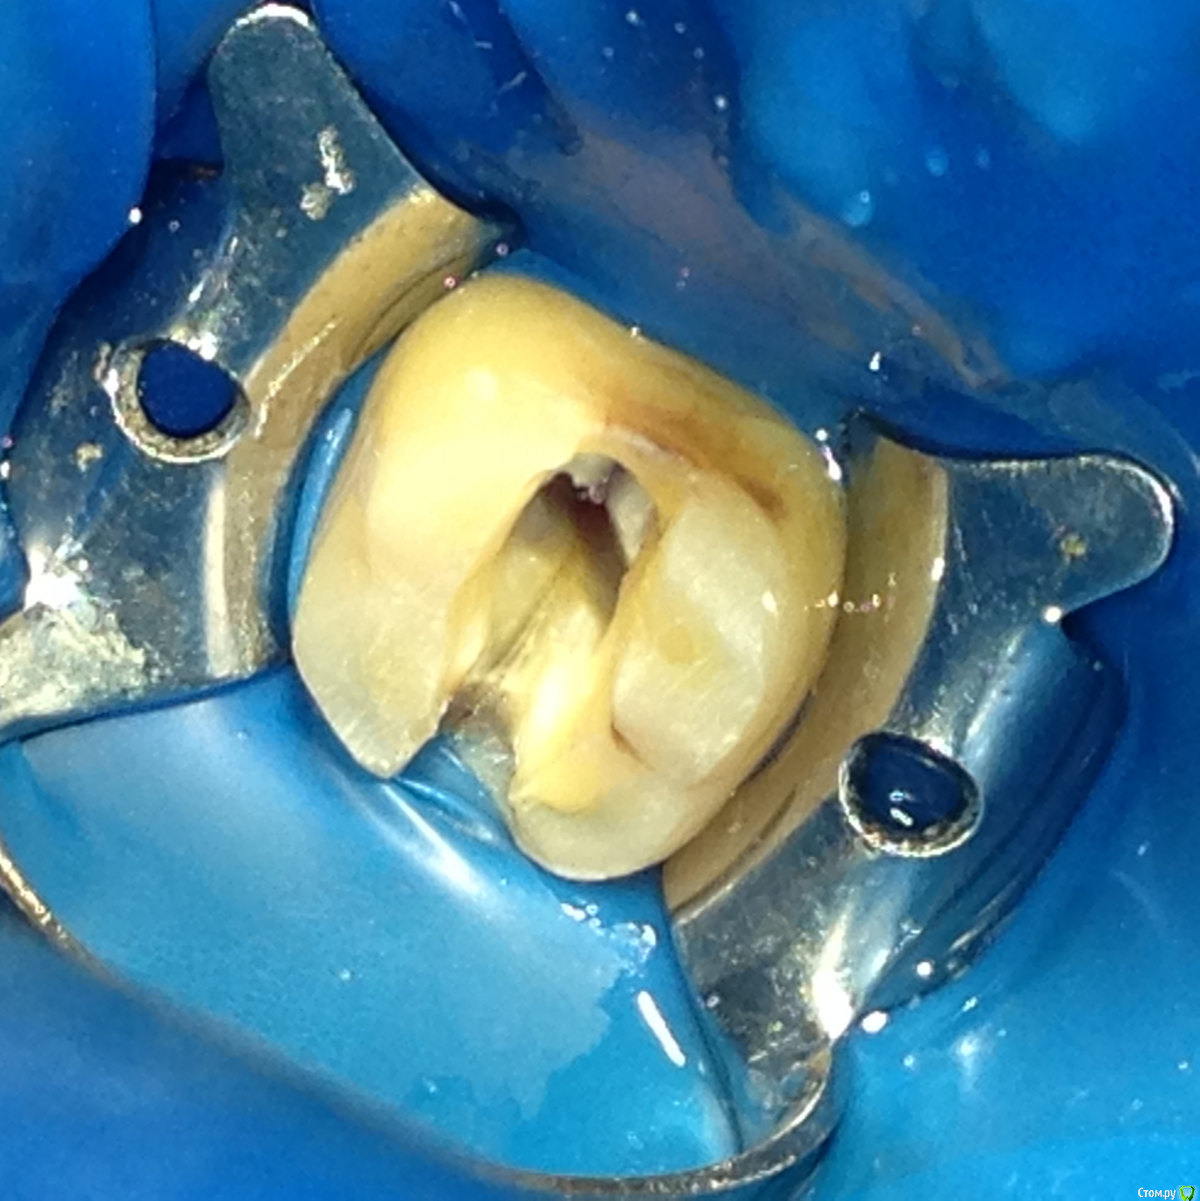

Salma Опубликовано 23 ноября, 2015 Поделиться Опубликовано 23 ноября, 2015 (изменено) Обратился сегодня пациент с жалобами на ноющие, боли при жевании в области 37 зуба. Пациент говорит, что какое то время при приеме пищи попала косточка на зуб и ощутил в этот момент острую боль. Обьективно: кариеса, пломб на зубе нет, на жевательной поверхности заметна продольная трещина, перкуссия болезненна, пальпация слабоболезненна, подвижность 1 степени, зондирование никаких карманов не выявило, на прицельном снимке незначительное расширение периодонтальной щели на всем протяжении. На эндофрост никакой реакции. Решили депульпировать. Отпрепарировала, вот такой вид, явная трещина дистального корня, трещины в области бифуркции или в области медиального корня я не нашла. Закрыла с кальцием. Вопрос собственно. что делать, какой прогноз если постараться оставить? Изменено 23 ноября, 2015 пользователем Salma Ссылка на комментарий

krokomot Опубликовано 24 ноября, 2015 Поделиться Опубликовано 24 ноября, 2015 А глубину на которую идет трещина как то проверили?Если ушла за цэс, то прогноз отвратителен и лечение можно провести только ради эксперимента. Если не ушла, то неагресивное эндо (максимум 4 конус и 30исо ) с пломбированием без давления. Никаких латералок и вертикалок. Одним штифтом. И полную постоянную коронку как можно быстрее.На фото видно что трещина точно доходит до уровня устья, а это уже ниже цэс, то есть по вашему прогноз сразу не благоприятный? Ссылка на комментарий